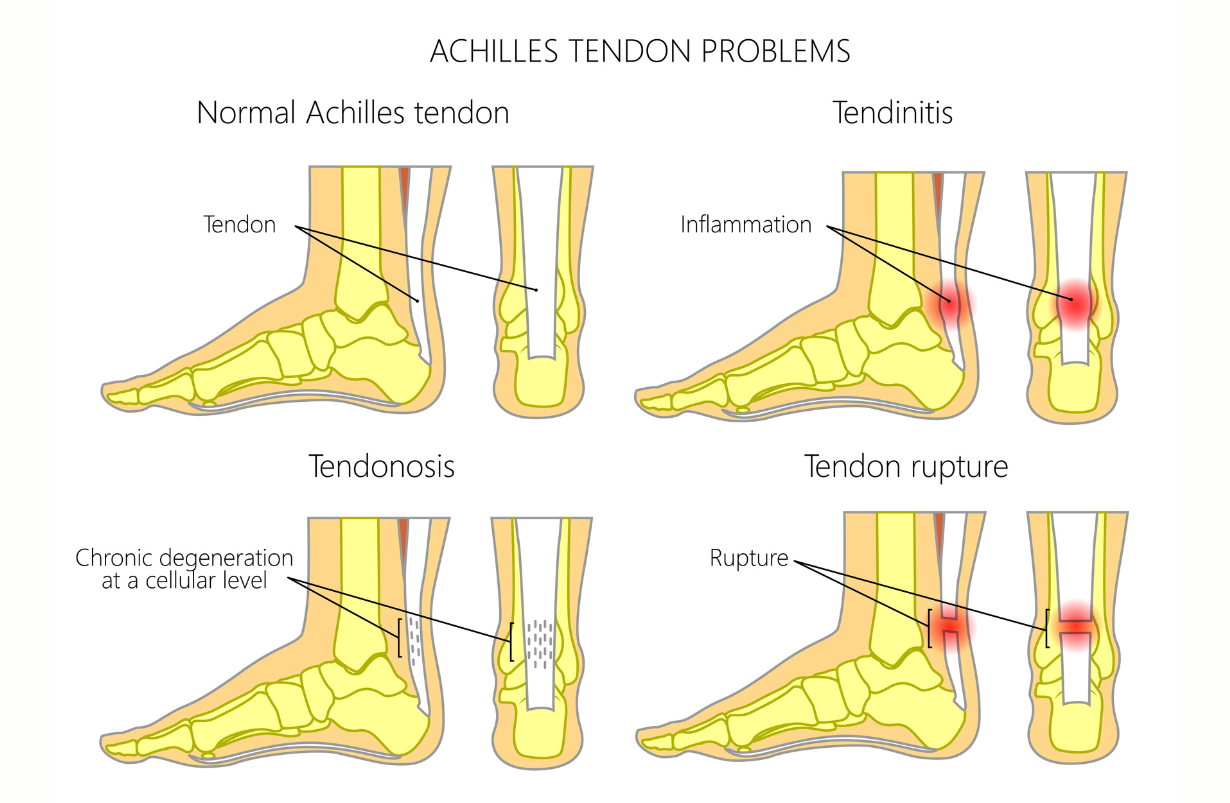

Achilles Tendinitis

Inflammation and/or painful strain or tearing of the Achilles tendon at the back of the heel. This is the tendon that enables you to walk, climb stairs, stand on your toes: to plantar flex your ankle.